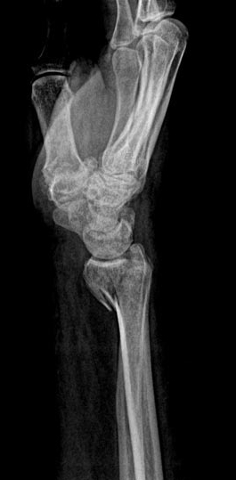

Unstable Volar Shear Fracture of Distal Radius